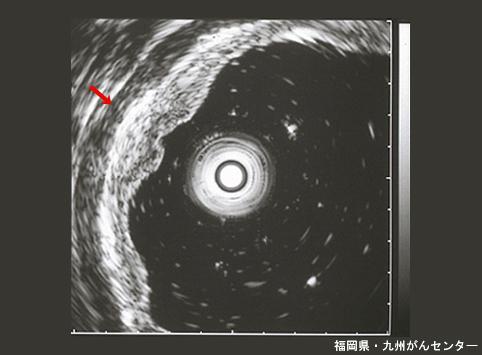

A case of superficial depressed type adenoma of the stomach which was removed by an endoscopic mucosal resection.

Fukuoka Pref., National Hospital Organization Kyushu Cancer Center

Benign epithelial tumor/Adenoma

Stomach/Antrum

Ultrasonography

Type 0/IIc (IIc) Superficial depressed type

10 - 14